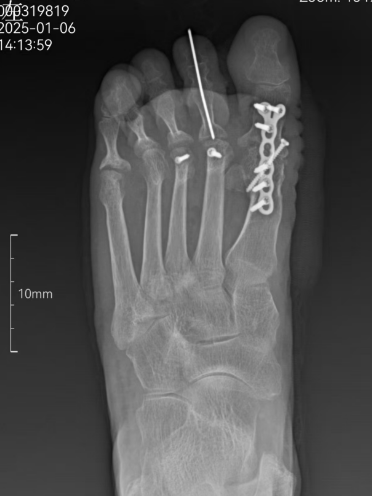

2025年1月,李阿姨来到了了杭州邦尔骨科医院的手足外科宋主任的门诊,她详细诉说了自己的病痛与无奈。宋主任耐心倾听,细致检查,随后安排了 X 线片检查。检查结果显示,李阿姨双足第 1 跖趾外翻畸形,左侧第 1 跖骨内翻畸形严重,双足拇趾外翻畸形矫正难度大。面对这复杂的病情,宋主任凭借多年丰富的临床经验,为李阿姨量身定制了一套详细的手术治疗方案。

术中,手足外科宋主任团队,以精湛的技艺和严谨的态度,为李阿姨实施了拇外翻手术。巧妙地矫正了李阿姨的足部畸形,重塑了足部的正常结构。术后,李阿姨的足部外观有了明显改善,疼痛感大幅减轻,看着自己曾经扭曲的脚趾重新变得整齐,她激动得热泪盈眶。